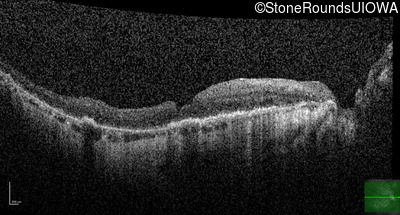

This 81 year old man began using a flashlight to read menus in his 40's. At age 75 his ophthalmologist noticed abnormal fundus findings and referred him to a retina specialist.

Diagnosis & molecular findings

| Late Onset Retinal Dystrophy | C1QTNF5 | Ser163Arg AGC>AGA | AD |